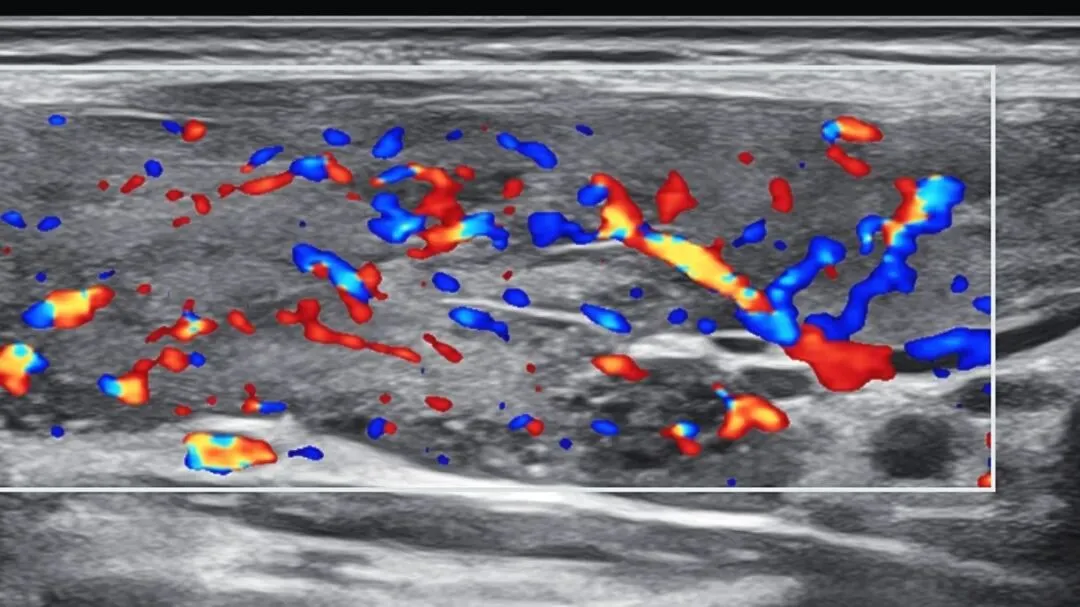

我们天天给别人扫结节,测血流信号,更要懂得:

健康没了,什么都没了。